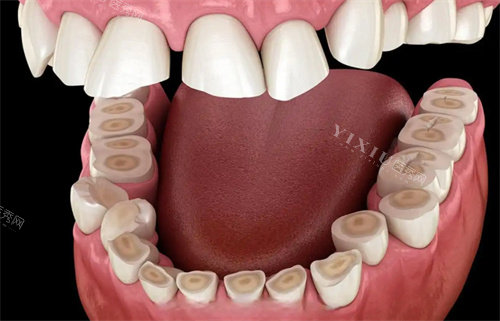

二楼:口腔内科(牙体牙髓、牙周、儿童口腔)

三楼:口腔外科(种植、颌面外科)、口腔矫形科(正畸、修复)